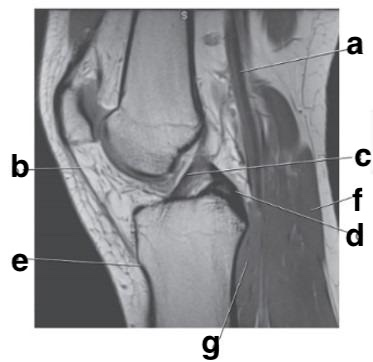

Medial meniscus

posterior cruciate ligament

Which letter is pointing to the posterior cruciate ligament?

e

b

medial collateral ligament

Which letter is pointing to the anterior cruciate ligament?

c